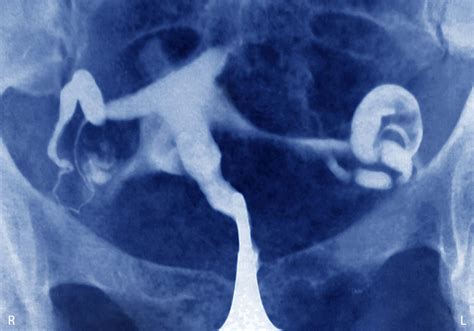

Weba progesterone level greater than 25 ng/ml (79. 5 nmol/l) almost always rules out the presence of an ectopic pregnancy. However, a progesterone level less than 5 ng/ml (15. 9 nmol/l) suggests either an ectopic pregnancy or an abnormal intrauterine pregnancy. Webstudy with quizlet and memorize flashcards containing terms like most definitive finding for ectopic is a _______ _______ outside of the uterus, what is the most emergent. Webdec 11, 2014 · ectopic pregnancy is a common and potentially fatal emergency in early pregnancy (1,2). Its prevalence is about 2% in the general population (2), but is as high.